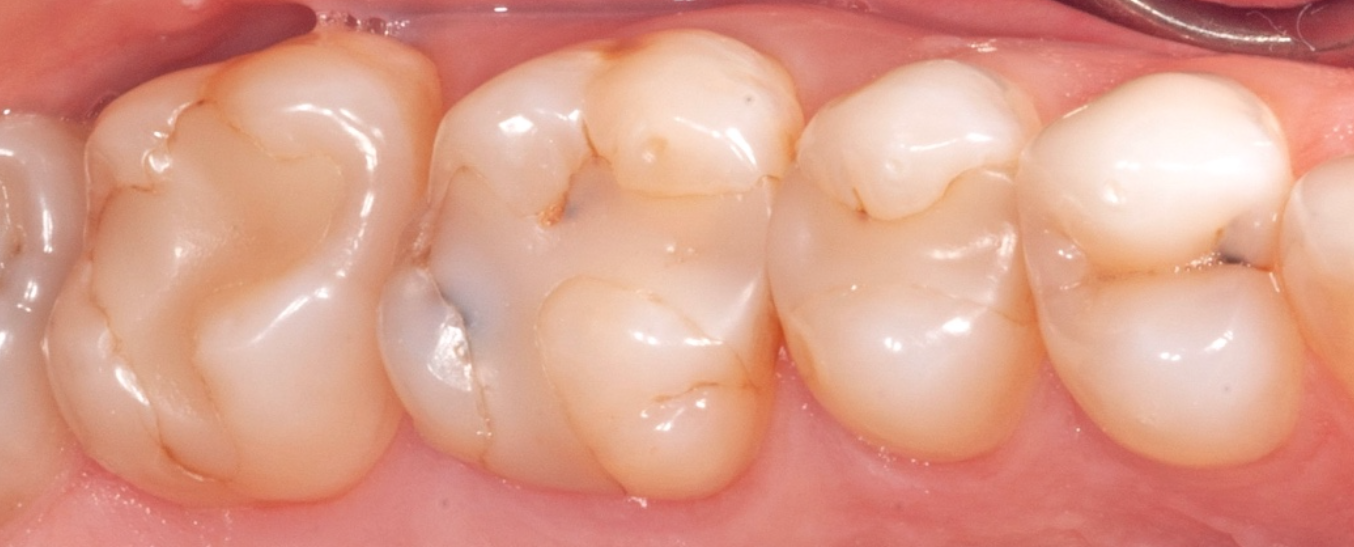

So what does this mean to our patients? It means that finally, we can truly practice minimally invasive dentistry, where we don’t have to cut teeth down to make them stronger. Teeth are strengthened from the inside out. We now just take away the old fillings and/or decay, thoroughly disinfect, and adhere the composite to the teeth, thus preserving their integrity and as a side benefit, increasing the probability of preventing abscesses. Although the costs are greater than the mercury-amalgam fillings, they are half to two-thirds the cost of buildups and crowns. This has totally changed the way dentistry is practiced today! Below are some photos which demonstrate this philosophy.

This first case is a female patient in her 50’s. She presented to us with significant wear on the lower anterior teeth, a sign of clenching and grinding of the teeth (bruxism). Normal and healthy anterior teeth have approximately 2 mm of enamel at their edges.

This presents both esthetic and decay concerns for our new patient. After discussing the root cause of this condition, and offering ways to prevent its recurrence, we offered her 3 options: (1) do nothing, (2) prepare (cut down) the teeth for veneers or crowns, or (3) perform Maximized Adhesive Dentistry (MAD) using composite. She chose the third option, and was thrilled with the result. This was performed in a single 3-hour appointment, and in this case without the use of local anesthetic.